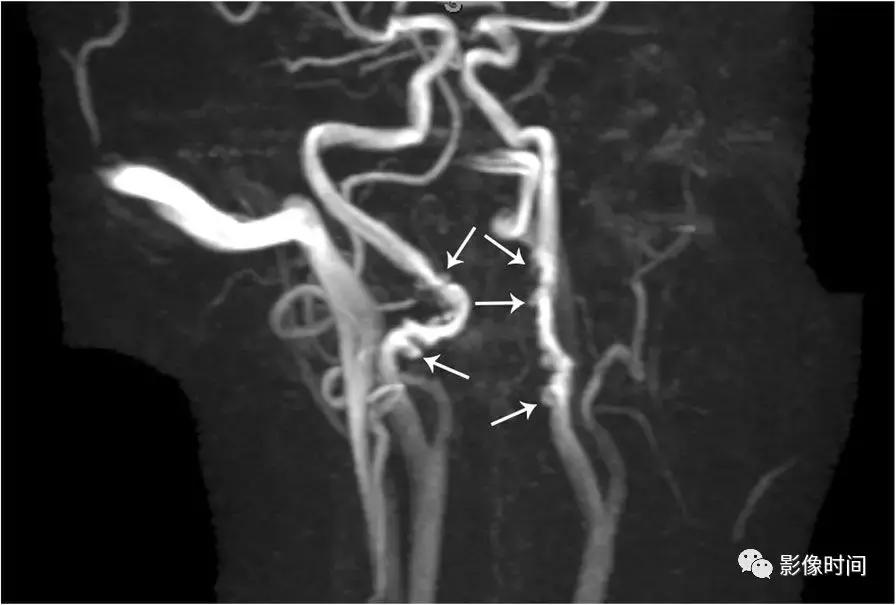

6.纤维肌性发育不良:颈动脉纤维肌性发育不良是一种罕见且无症状的疾病,因此往往是偶然发现的。然而,有症状的病人可以出现脑梗死、短暂缺血、或蛛网膜下腔出血。虽然纤维肌性发育不良可发生在三层动脉壁中的任何一层,但中膜受累是最常见的表现。超过 90% 的病例动脉壁由于纤维增厚和弹性层的破坏而而导致多灶性狭窄和扩张。值得注意的是管腔扩张往往大于正常血管直径,从而有助于区分纤维肌性发育不良和动脉粥样硬化。「串珠」外观在 80% -90% 的病例中都能看到。CTA 和 MRA 是首选检查。

模式图显示纤维肌性发育不良的主要亚型:1 型表现为收缩和扩张的交替;2 型表现为管状狭窄,3 型表现为局灶性波纹+憩室。MRA 显示双侧颈内动脉「串珠」外观(箭头)。CTA 和 DSA 亦显示颈内动脉「串珠」外观。